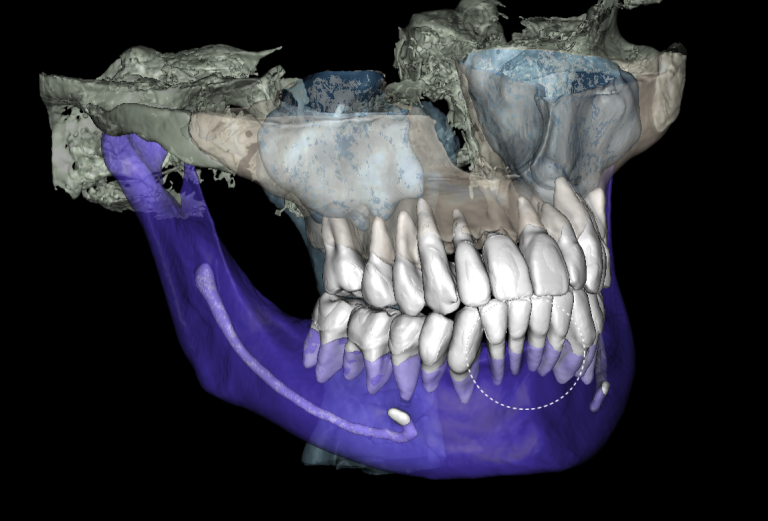

Diagnocat determined not only the presence, but also the localization of the focus of radiolucency of enamel and dentin, which was correctly indicated as “signs of caries” in the report

Please note that despite the fact that the radiolucent area is poorly visible when viewing CBCT, Diagnocat reflected in the report the presence of signs of caries and accurately indicated the localization